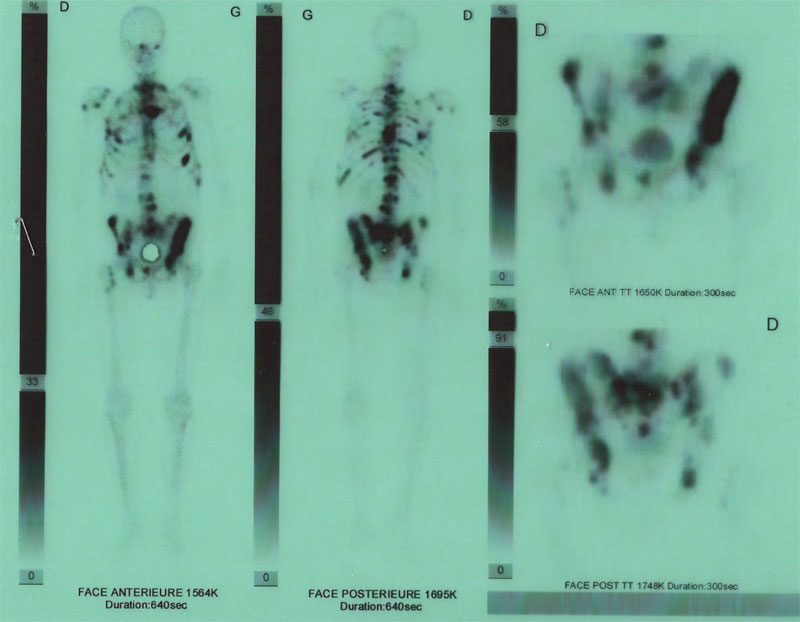

Six mois plus tard, douleurs de dos persistantes. Le généraliste, devant l’insistance du patient fait quand même faire une analyse de sang : PSA à 310. Biopsie et scintigraphie osseuse : cancer de la prostate grade Gleason 9 avec métastases osseuses : médiane de vie entre 6 mois et 14 mois.